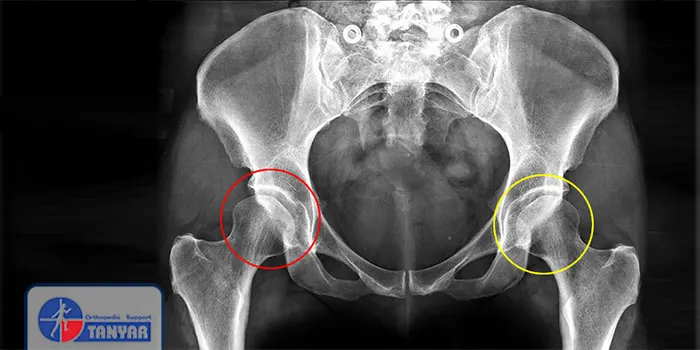

تشخیص دیسپلازی مفصل ران معمولاً از طریق یک معاینه فیزیکی دقیق آغاز میشود. پزشک با معاینه وضعیت پاها و مفاصل نوزاد میتواند مشکلاتی را شناسایی کند. بهعلاوه، استفاده از سونوگرافی برای نوزادان کمسن یکی از روشهای مؤثر در تشخیص زودهنگام دیسپلازی مفصل ران محسوب میشود. این روش به پزشک کمک میکند تا وضعیت مفصل و ساختار آن را با دقت بررسی کند. رادیوگرافی یا اشعه ایکس نیز ممکن است در تشخیصهای پیشرفتهتر و در زمانهایی که نوزاد کمی بزرگتر میشود، مورد استفاده قرار گیرد. این تصاویر به ارائه نمای واضحتری از وضعیت مفاصل و استخوانهای نوزاد کمک میکنند. در نهایت، ممکن است پزشک تستهای تشخیصی دیگر نیز برای تأیید نهایی وضعیت مفصل و برنامهریزی درمانی بهکار ببرد.